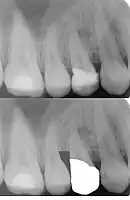

بالإضافة إلى ذلك، يمكن اللجوء إلى التدخل التقويمي لبثق الأسنان كعملية بديلة عن التطويل التاجي الجراحي؛ وتعتبر هذه الطريقة غير باضعة ولا تزيل أو تضر العظم على الإطلاق وأقل تكلفة. في التدخل التقويمي لبثق السن، يتم بثق السن لعدة مليمترات عن طريق الاستناد البسيط على الأسنان المحاذية للسن المراد بثقه وباستخدام قوة بسيطة وقد تستغرق هذه العملية عدة شهور. بعد أن تتم عملية التطويل التاجي بالتدخل التقويمي يتم قطع الألياف المحيطة بالسن، وعادة ما يقوم بهذا الإجراء طبيب الأسنان العام. في حال استخدام التقويم في العلاج بدلاً من علاج دواعم السن يجب عدم اللجوء إلى الجراحة والقلع كما هو موضح في الصورة المجاورة.